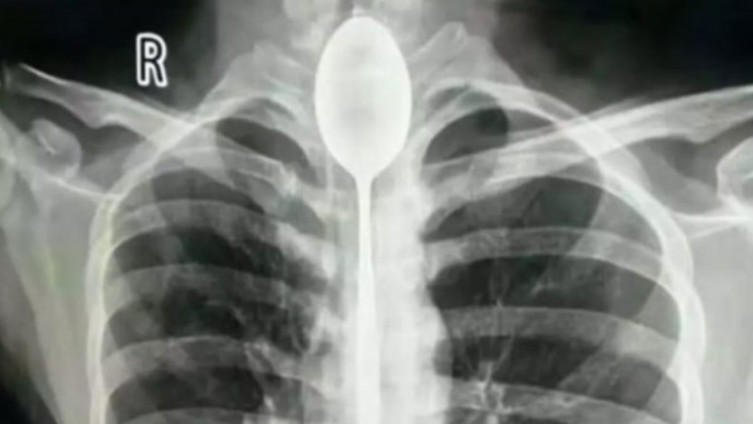

Kinez godinu dana živio sa 20 centimetara dugom kašikom u grlu

Kineske ljekare šokirao je slučaj pacijenta koji se požalio da jedva diše. Naime, na rendgenu su primijetili kašiku dužine 20 centimetara u grlu muškarca, a što je još čudnije, mjesecima mu nije mnogo smetala.

Mladić dvadesetih godina htio je da impresionira prijatelje gutanjem pribora za jelo, i sve je bilo “u redu” dok ga neko nedavno nije udario u grudi.

Ljekarima je trebalo dva sata da uklone strani objekat iz jednjaka čovjeka koji se previjao u bolovima, ali je na kraju sve prošlo kako treba.

Jedan od ljekara kaže da je bio veoma iznenađen i da nikada nije vidio nešto ovakvo. Također navodi da je mladić imao mnogo sreće jer je gutanje ovako velikih predmeta opasno po život.